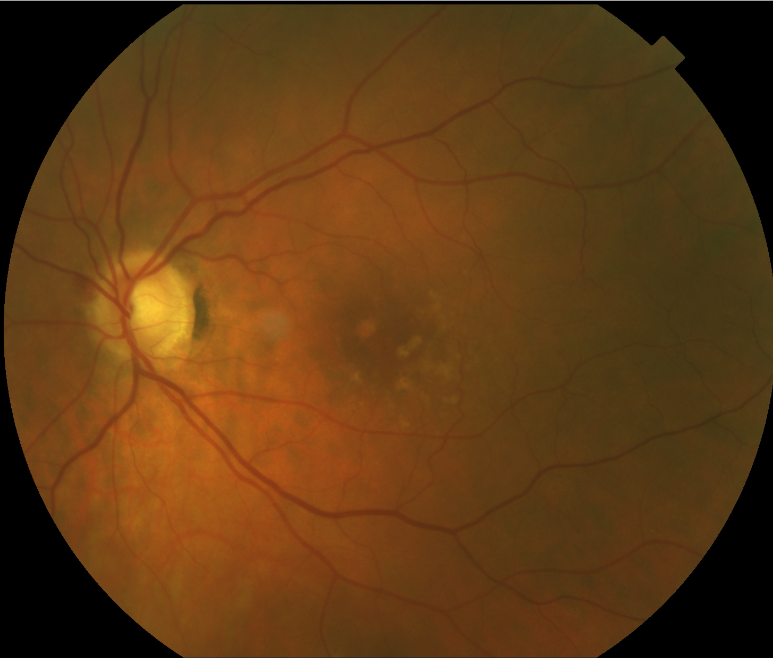

FUNDUS DESCRIPTION: |

OD OS |

OD Red-Free: Pre-Injection: Arterial: A-V: Venous: Recirculation: Late:

OS Red-Free: Venous: Recirc: Late:

Impression